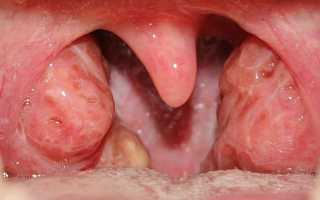

Такие симптомы имеет катаральная форма ангины, развивающейся на фоне лейкоза. Если заболевание протекает в более тяжёлой, лакунарной, фибринозной или гангренозной форме, у больных отмечаются язвенно-некротические изменения в горле, иногда сопровождающиеся проявлениями подострого или острого гингивита. Из внешних проявлений присутствуют язвенные поражения десен и серовато-жёлтые или белёсые налёты в горле, которые очень трудно отделяются от слизистой и оставляют после себя кровоточащие, не заживающие длительное время, участки. Эти визуальные признаки свидетельствуют о развитии злокачественного процесса.

- Фарингоскопия. Визуальный осмотр зева. Изменения миндалин при лейкозе первоначально соответствуют катаральной форме ангине, тонзиллита. По мере прогрессирования болезни они утяжеляются, и в ближайшее время у пациента развивается язвенно-некротическое или гангренозное поражение. На заключительных этапах болезнь характеризуется наличием патологических признаков во всей полости рта, десен, глотки.